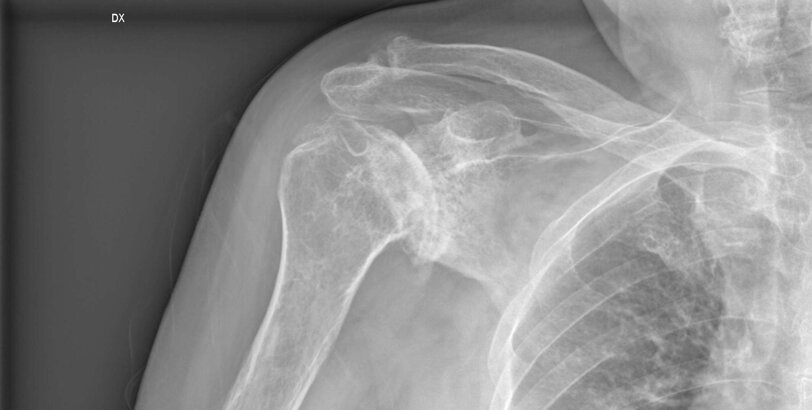

LUSSAZIONI DI SPALLA

L'articolazione della spalla ricorda una sfera (testa dell'omero) che si adatta in un guscio (glena). La testa dell'omero viene trattenuta nella glena dai muscoli della spalla e dalla "capsula" (una sorta di manicotto fibroso), che si inserisce sul contorno della glena tramite un anello di cartilagine: il "labbro glenoideo". Quando la capsula viene danneggiata in seguito ad un trauma oppure si presenta più debole per costituzione, essa non è più in grado di trattenere efficacemente la testa dell'omero nella glena e la spalla diventa "instabile"; durante certi movimenti del braccio la testa dell'omero si muove allora in maniera anomala e comunque eccessiva rispetto alla glena, tanto da provocare dolore e senso di instabilità ("sublussazione"); in alcuni casi la testa dell'omero e la glena perdono del tutto il reciproco contatto ("lussazione").

L'instabilità traumatica di spalla è spesso dovuta ad una caduta; la testa dell'omero si sposta in una particolare direzione (generalmente in avanti: è la cosiddetta "lussazione anteriore di spalla") e di solito lacera la capsula oppure disinserisce il labbro glenoideo dalla glena ("lesione di Bankart"). In genere il riposizionamento della testa omerale nella sua cavità viene effettuato in urgenza da un medico che deve anche valutare l'eventuale presenza di danni neurologici, vascolari o ossei. La spalla viene poi immobilizzata per un periodo di 2-4 settimane nel caso di un primo episodio. La riabilitazione inizia alla rimozione del bendaggio con movimenti delicati, evitando di forzare l'abduzione e la rotazione esterna. A 3 settimane dalla rimozione del bendaggio si potrà iniziare, previo parere del medico, a guidare, mentre l'attività lavorativa richiede di solito almeno altre 2 settimane. In questo periodo assume molta importanza la riabilitazione propriocettiva (serve per ottenere un buon controllo sulla coordinazione muscolare). A circa 2 mesi dal trauma viene perfezionato il recupero globale, a circa 3 mesi dal trauma si può riprendere l'attività sportiva. Purtroppo durante la prima lussazione traumatica si verificano molto spesso dei danni permanenti nella spalla (come una lacerazione o un allentamento della capsula o la già citata "lesione di Bankart", attraverso la quale la testa omerale può nuovamente impegnarsi): perciò può accadere che dopo la riabilitazione. persistano una sensazione di instabilità o che, più frequentemente, si manifestino nuove lussazioni. In tali casi la rieducazione va continuata, ma si deve iniziare a prendere in considerazione il trattamento chirurgico, soprattutto nei pazienti più attivi, per i quali è maggiore il rischio di una nuova lussazione (recidiva).